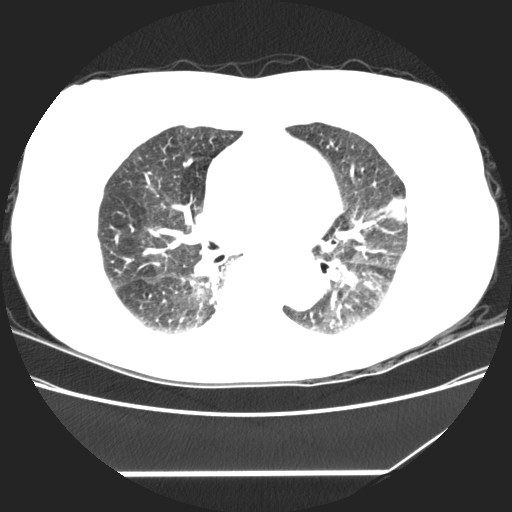

女性,62岁,长期咳嗽,既往从事工作有粉尘接触,有高血压病史,110/150mmhg,近日咳嗽加重,脸面浮肿,请大家帮看下,

1、尘肺;2、慢性支气管炎合并肺部感染;3、心影增大(左房、左室大),考虑高血压性心脏病。

间质性肺炎,有纤维化趋势。

1)慢性支气管炎并肺部感染、肺气肿。2)肺间质纤维化。

间质性肺炎,左下肺机化性肺炎。